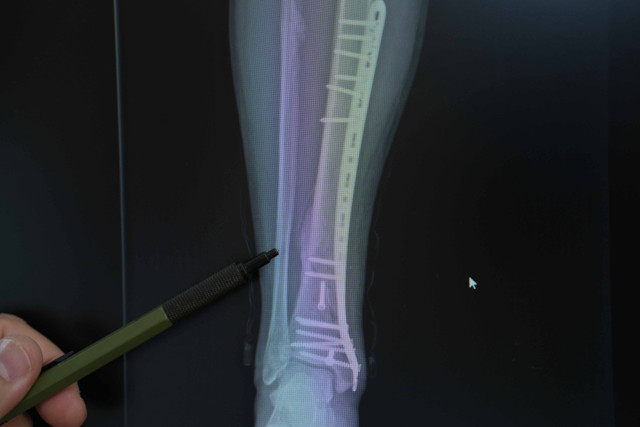

Abone olTrafikte motosikletlerin sayısı her geçen gün artıyor, ancak bu artış kazalar ve yaralanmalarda da belirgin bir yükselişi beraberinde getiriyor. Medipol Üniversitesi Pendik Hastanesi’nden Ortopedi ve Travmatoloji Uzmanı Dr. Öğr. Üyesi Mehmet Soyarslan, motosiklet kazalarının çoğunda kırık ve yumuşak doku hasarlarının görüldüğünü belirterek, “Eğitimsizlik, koruyucu ekipman eksikliği ve bilinçsiz kullanım, en büyük tehlike kaynağı. Acile başvuran motosiklet kazalarının yaklaşık yarısında kas iskelet sistemi hasarı, bu olguların da yüzde 30-40’ında kırıklar görülüyor” uyarısında bulundu.

Türkiye’de trafiğe kayıtlı 6,5 milyondan fazla motosiklet bulunduğunu vurgulan Dr. Soyarslan, “Bazı illerde, motosiklet sayısı artık otomobil sayısını geçmiş durumda. Pandemidöneminde hızla büyüyen kurye sektörü bu artışta büyük rol oynadı. Büyük şehirlerde ise trafik ve park sorunundan kaçmak için bireysel kullanım yaygınlaştı. Eskiden acillerde düşme ya da araç çarpışması nedeniyle yaralanmaları görürdük, şimdi motosiklet kazaları açık ara önde. Bu kazalar sadece kırıklarla değil, kafa, göğüs ve karın travmalarıyla da karşımıza çıkıyor” dedi.